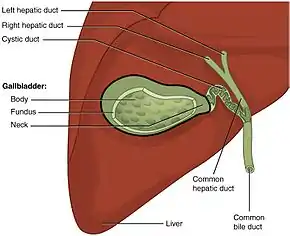

In vertebrates, the gallbladder, also known as the cholecyst, is a small hollow organ where bile is stored and concentrated before it is released into the small intestine. In humans, the pear-shaped gallbladder lies beneath the liver, although the structure and position of the gallbladder can vary significantly among animal species. It receives bile, produced by the liver, via the common hepatic duct, and stores it. The bile is then released via the common bile duct into the duodenum, where the bile helps in the digestion of fats.

Structure

The gallbladder is a hollow grey-blue organ that sits in a shallow depression below the right lobe of the liver.[2] In adults, the gallbladder measures approximately 7 to 10 centimetres (2.8 to 3.9 inches) in length and 4 centimetres (1.6 in) in diameter when fully distended.[3] The gallbladder has a capacity of about 50 millilitres (1.8 imperial fluid ounces).[2]

The gallbladder is shaped like a pear, with its tip opening into the cystic duct.[4] The gallbladder is divided into three sections: the fundus, body, and neck. The fundus is the rounded base, angled so that it faces the abdominal wall. The body lies in a depression in the surface of the lower liver. The neck tapers and is continuous with the cystic duct, part of the biliary tree.[2] The gallbladder fossa, against which the fundus and body of the gallbladder lie, is found beneath the junction of hepatic segments IVB and V.[5] The cystic duct unites with the common hepatic duct to become the common bile duct. At the junction of the neck of the gallbladder and the cystic duct, there is an out-pouching of the gallbladder wall forming a mucosal fold known as "Hartmann's pouch".[2]